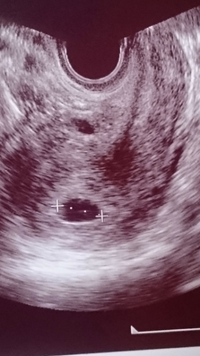

これは胎嚢ではないのでしょうか こんにちは 私は 妊娠希望で病院 妊娠 教えて Goo

これは胎嚢でしょうか エコー画像貼付します Okwave

これは胎嚢ではないでしょうか W 妊娠検査薬で陽性だったた 妊娠 教えて Goo